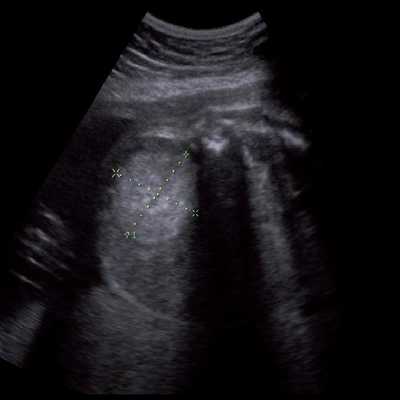

Под диафрагмой справа визуализировалось гиперэхогенное опухолевидное образование несколько неоднородной солидной структуры, с четкими ровными контурами, размером 50x38x35 мм. К нижнему полюсу данного образования прилежала правая почка, имеющая нормальные размеры, форму и структуру. Нижняя полая вена была смещена кпереди и влево. Обращала на себя внимание выраженная гепатомегалия, причем структура печени не была однородной. Она содержала множественные гиперэхогенные включения размерами до 17 мм, окруженные тонким гипоэхогенным периферическим ободком. Цветовое допплеровское картирование(ЦДК) демонстрировало интенсивную периферическую васкуляризацию опухоли (рис. 1-3).

Рис. 1. Нейробластома правого надпочечника плода. Беременность 31 нед 4 дня.